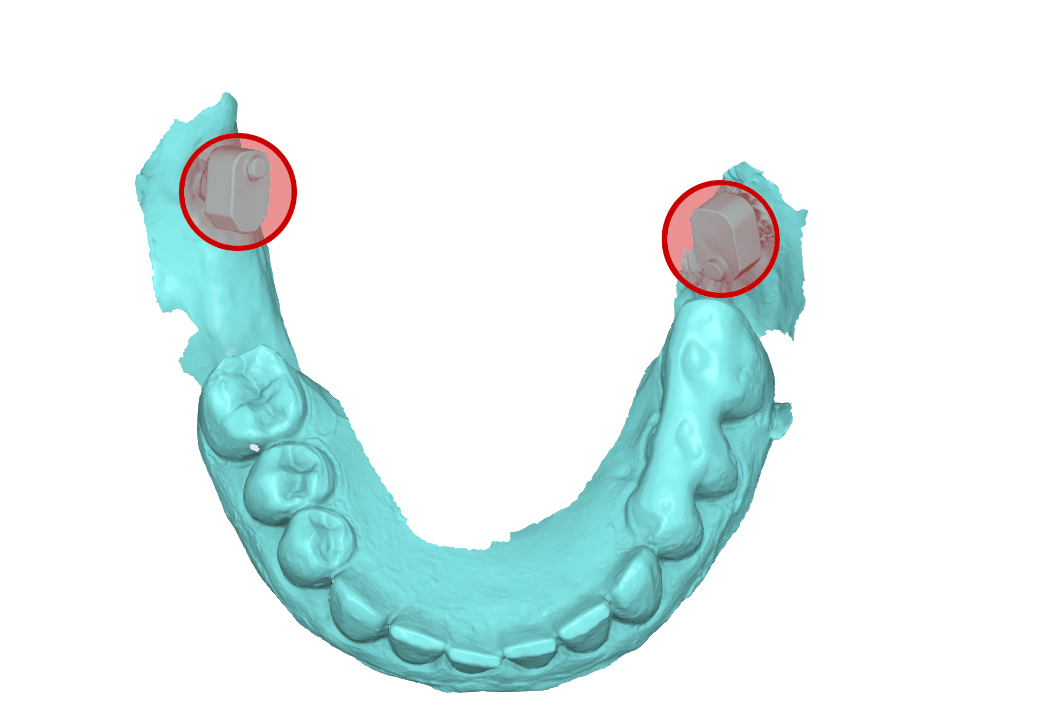

rendering 3D della scansione rilevata in massima intercuspidazione

Fig. 5. (b) rendering 3D della scansione rilevata in massima intercuspidazione, in evidenza lo ScanSke sinistro.

file .stl dell’impronta inferiore

Fig. 5. (c) file .stl dell’impronta inferiore, in evidenza gli ScanSke.

Fig. 7. (b) File .stl dell’impronta inferiore rilevata con dima di scansione universale e scanbody implantari, in evidenza gli ScanSke.

file .stl dell’impronta inferiore delle mucose

Fig. 7. (c) File .stl dell’impronta inferiore delle mucose, in evidenza gli ScanSke.

file .stl della sovrapposizione delle tre scansioni

Fig. 8. (a) file .stl della sovrapposizione delle tre scansioni, in evidenza gli ScanSke